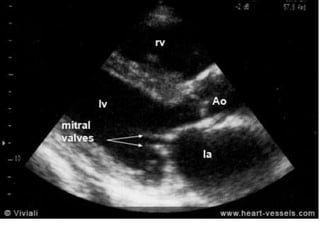

Views

1. PLAX

2. PSAX at MV level

3. A4CV

2 Dimensional (Initial Assessment)

• Restricted motion and diastolic motion of

leaflets ( hockey stick sign)

• Thickening and calcification of leaflets and

chordae